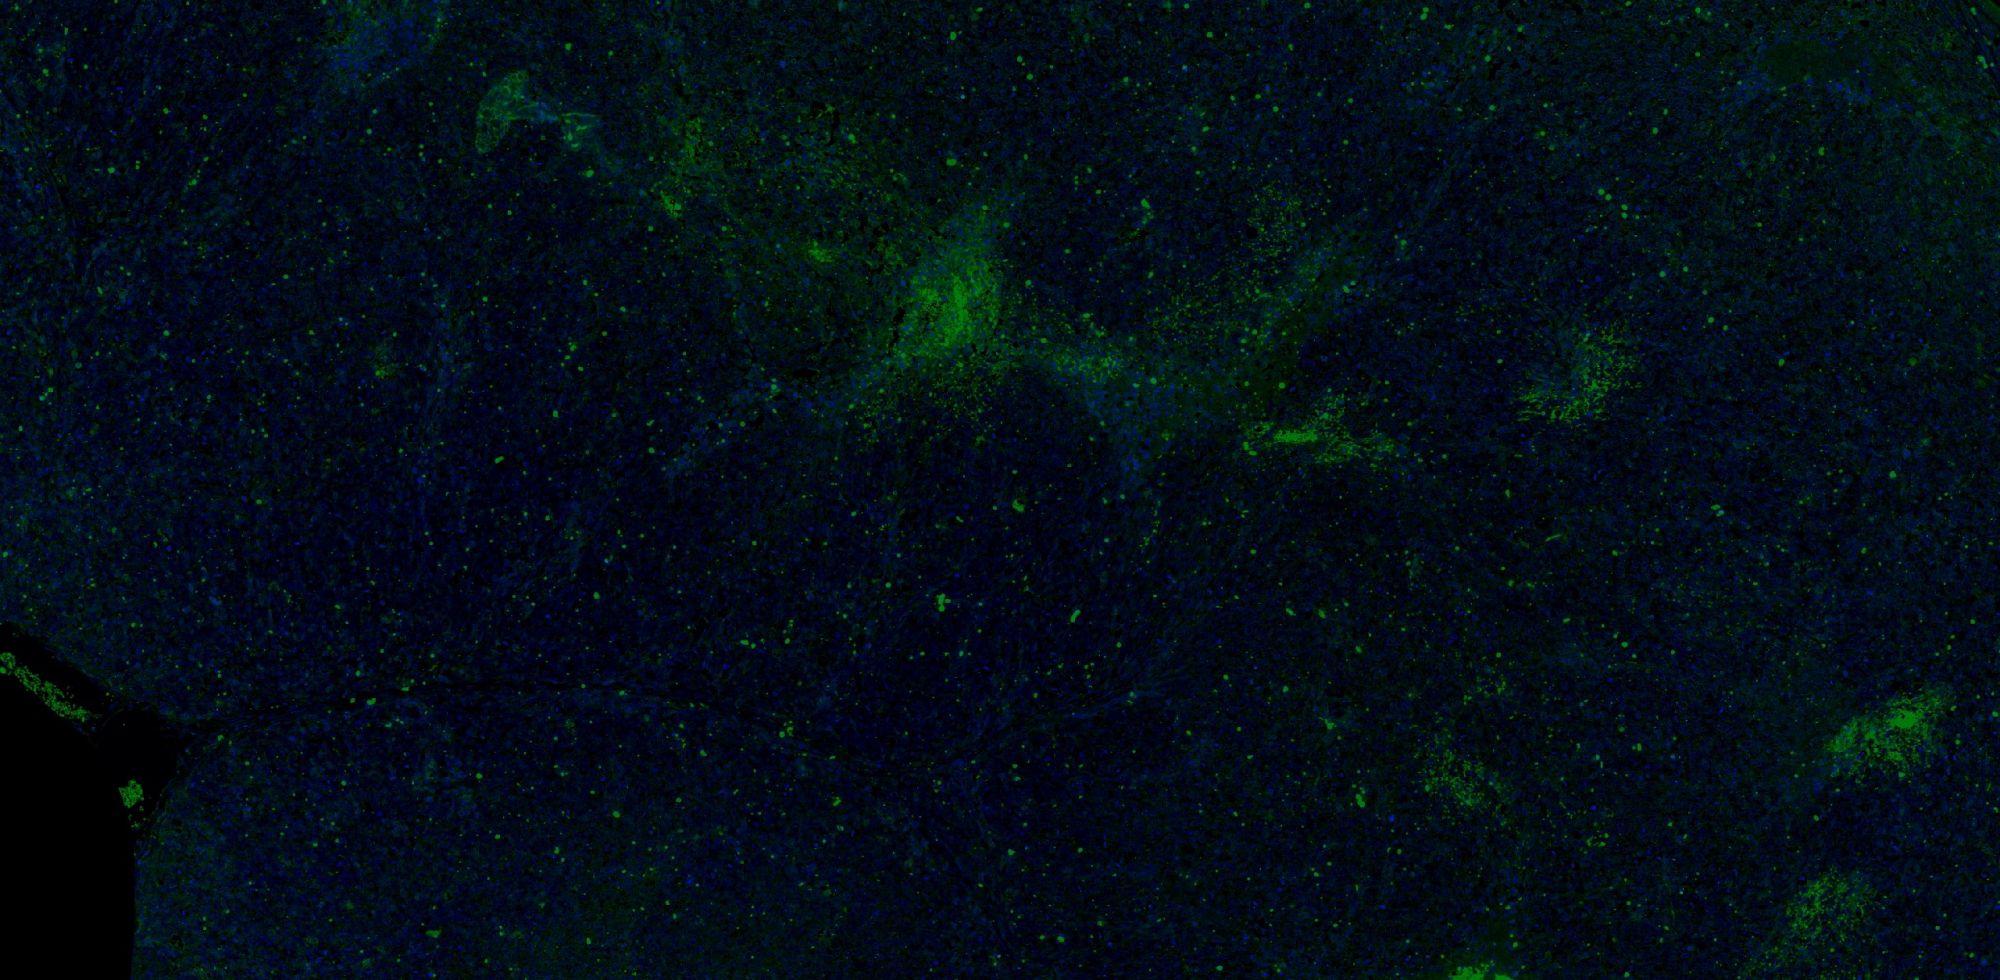

【技術(shù)原理】

免疫學(xué)的基本反應(yīng)是抗原-抗體反應(yīng)。由于抗原抗體反應(yīng)具有高度的特異性,所以當(dāng)抗原抗體發(fā)生反應(yīng)時,只要知道其中的一個因素,就可以查出另一個因素。免疫熒光技術(shù)就是將不影響抗原抗體活性的熒光色素標(biāo)記在抗體(或抗原)上,與其相應(yīng)的抗原(或抗體)結(jié)合后,在熒光顯微鏡下呈現(xiàn)一種特異性熒光反應(yīng)。

案例展示